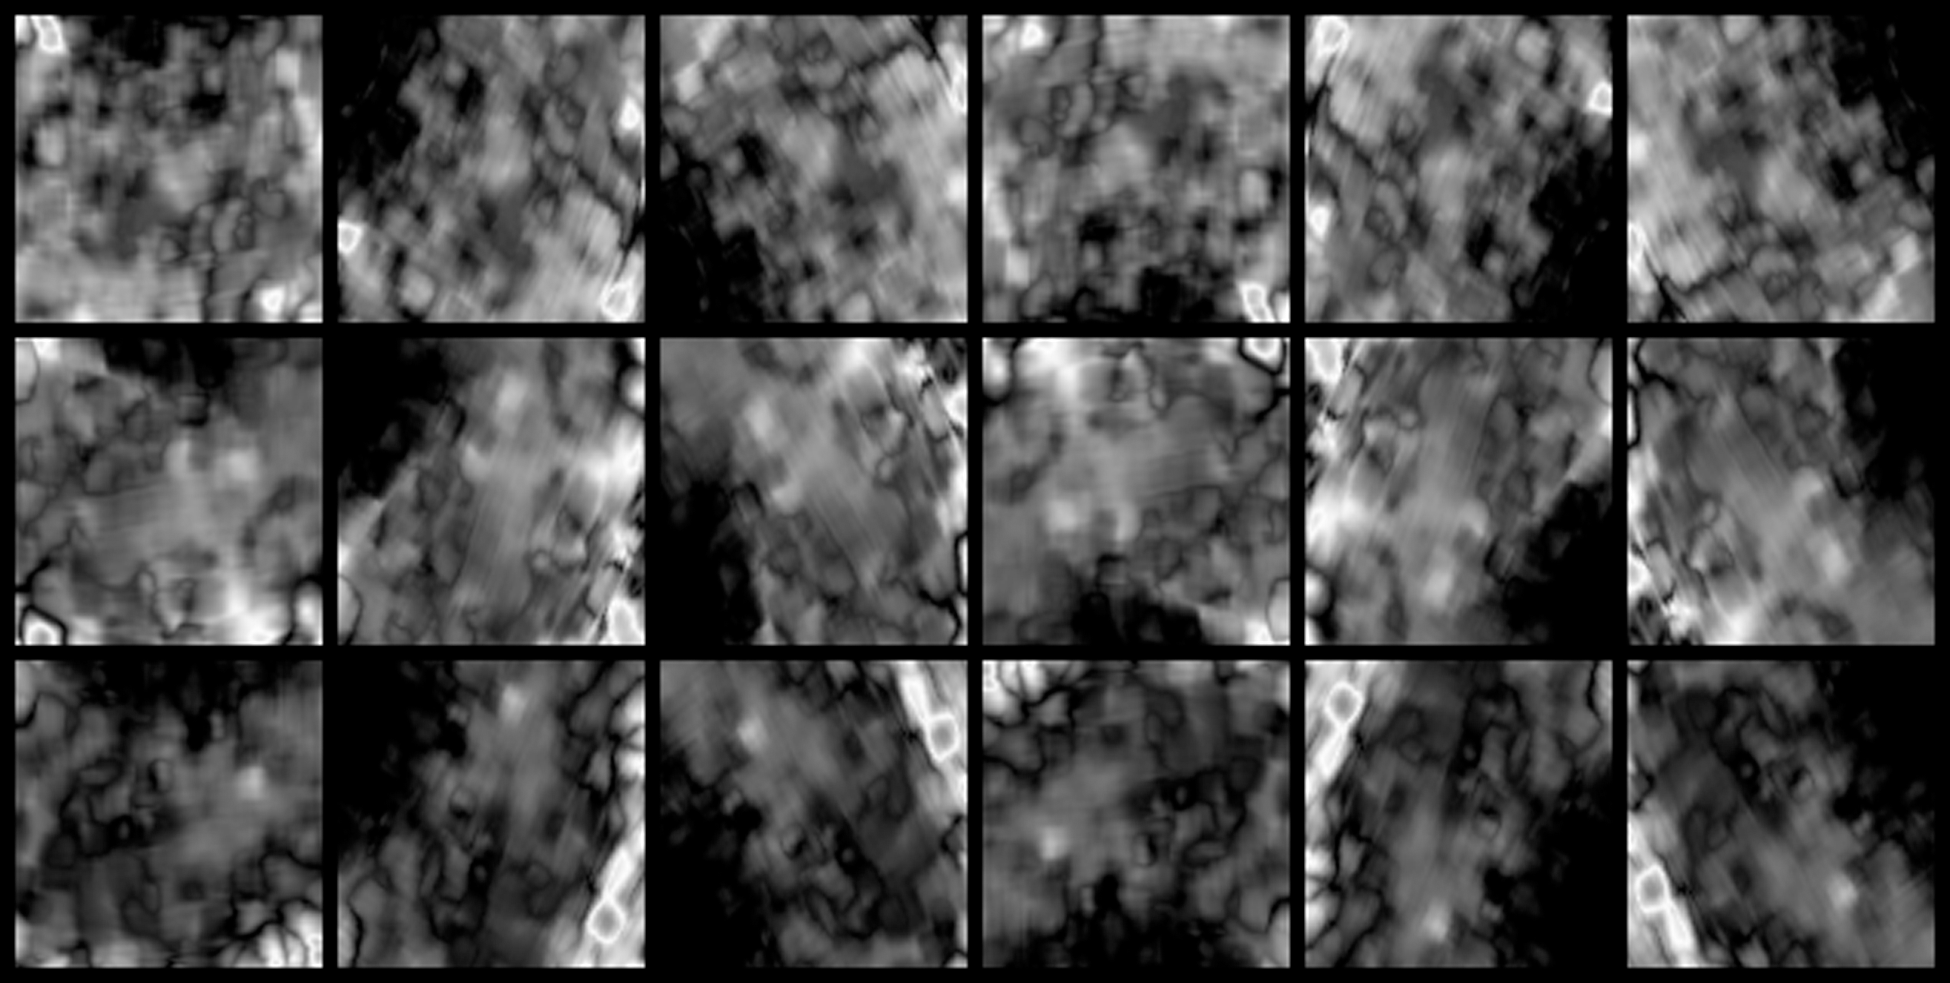

An averaging filter of 5 × 5 pixels is applied to the ultrasonic images as preprocessing. An average image is generated every second from the movie file by calculating an average for a time axis. 30 images are generated from 30 second movie by this process. An endometrial region is extracted from the average image by using a mask image. The mask image is as same as Section 3. Since an endometrial shape and direction have individual differences the extracted region size is different from each other. Rotation processes every 60 degrees is applied to the extracted images. The obtained image is saved in 224 × 224 pixels. Each pixel’s movement distance for one second is calculated as speed per second by applying an optical flow to the saved images. The calculated speeds are normalized to generate input images for a CNN. Speed statistics for the dataset are calculated to set a standard of normalization. The speed information is calculated for 19 successful subjects’ images. The fastest speed value in one image is recorded. A histogram for the obtained speed value is shown in Fig. 9. An average value of the calculated speed is 0.78 mm/sec and a standard deviation is 0.38 mm/sec. The calculated average value is generally consistent with 0.68 mm/sec show in previous study [13]. A normalized filter shown in Fig. 10 is generated based on the average and standard deviation. A velocity image is generated from the velocity information by using this filter. Fig. 11 shows an example of the velocity images. A vertical axis in Fig. 11 shows time of movie file, and horizontal axis shows rotated images. The number of the saved images is as same as Tab. 4.

Figure 11: Example of the saved velocity images